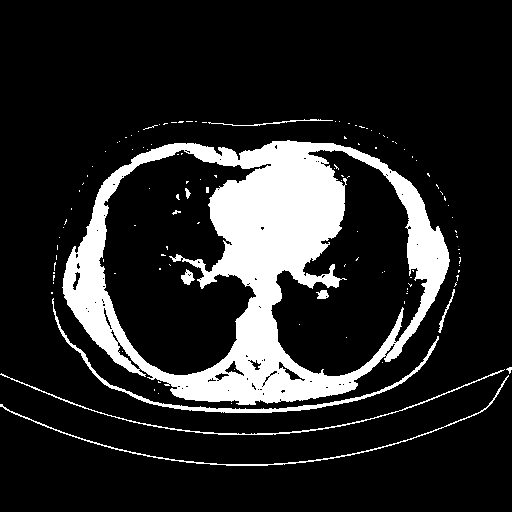

Image Grid

4Γ—3 grid: Rows show different image types (Original NATIVE, Reconstructed NATIVE, Original VENOUS, Generated VENOUS), Columns show windowing techniques (No Window, Lung Window, Mediastinum Window)

Reconstructed NATIVE CT scan (cycle consistency)

Mediastinum window (WL 40, WW 400 β†’ Low βˆ’160, High +240)

Actual HU range: [-160.0, 240.0]

Original VENOUS CT scan

Generated VENOUS CT scan (A→B translation)